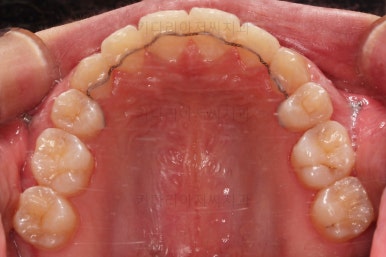

초진 시 입안의 모습이에요. 치열이 많이 나쁜 편은 아니고 앞니쪽이 조금 삐뚤어져 있네요.

특히 윗니 작은 앞니 하나가 아랫니보다 안으로 쑥 들어가 있어서 옆에 있는 송곳니가 덧니처럼 보여요.